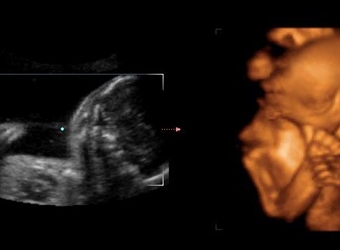

在国外据说有根据NT超声的图片来判断男女的方法,外国人称这种判断法为nub theory,那么英国nub原理看男女准不准呢,nub平行一定是女宝吗?更多关于生男生女的…

在国外有通过宝宝的超声图来判断男女性别的办法,也就是nub点看男女,那么12周男宝宝特点NT值是什么呢,用nub点看男女准不准?更多关于生男生女的相关内容尽在…